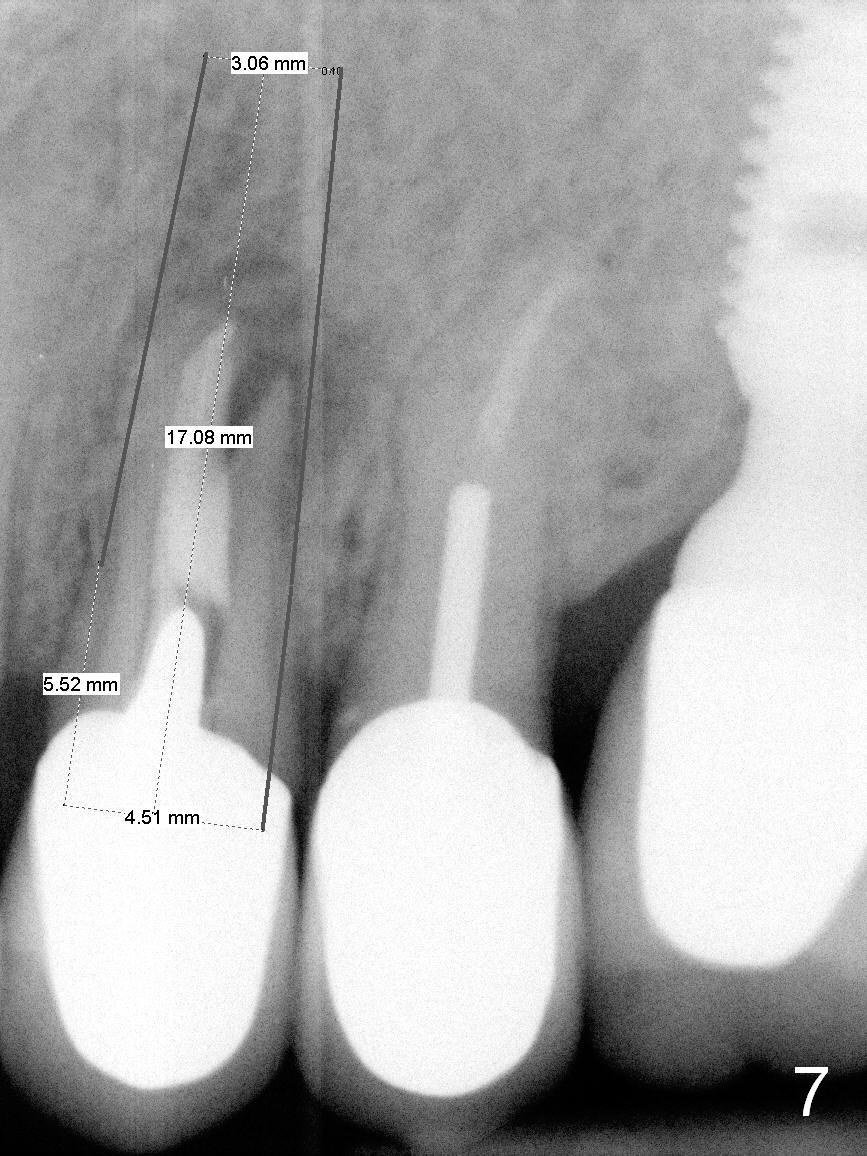

A 4.5x14 mm bone-level or 4.5x17 mm tissue-level implant appears to be appropriate for the site according to the PA (Fig.6,7). CBCT shows that there is enough bone to place a 4.5x20 mm tissue-level implant (Fig.8). This is more appropriate, considering the large radiolucency (Fig.5), the age of the patient (possibly osteoporosis), and the maxilla (bone softer than that of the mandible). The implant will be supported by approximately 8 mm solid bone apically (Fig.8).

In addition, osteotomy will be under prep. The depth of a 2 mm pilot drill, 2.5 mm and 3 mm reamers will be 20 mm, 17 mm and 14 mm, respectively. A 4.5x20 mm tap will be inserted 17 mm before placing the corresponding implant. Intraop PAs are to be taken following the pilot drill, tap and implant.